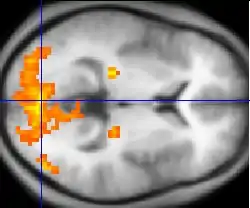

fMRI is particularly important because it allows for detailed functional mapping of the human brain. fMRI measures blood oxygen level dependent (BOLD) contrast, which allows us to view the most active areas of the brain at a given moment based on blood flow. This imaging modality allows researchers to identify and understand complex neural pathways and mechanisms. Relevant mechanisms in neurolaw research are memory, reward, impulse, and deceit circuitry.

fMRI imaging is also being used to analyze brain activity during intentional lies. Findings have shown that the dorsolateral prefrontal cortex activates when subjects are pretending to know information, but that the right anterior hippocampus activates when a subject presents false recognition in contrast to lying or accurately telling a truth. This indicates that there may be two separate neural pathways for lying and false memory recall. However, there are limitations to how much brain imaging can distinguish between truths and deceptions because these regions are common areas of executive control function; It is difficult to tell if the activation seen is due to the lie told, or something unrelated.[32]